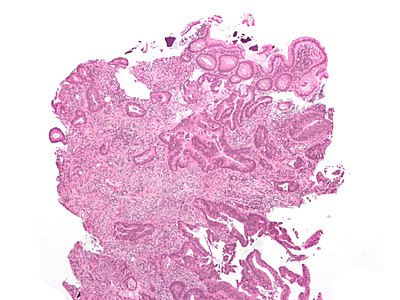

8

Diagnosis?

Traditional serrated adenoma low mag.jpg

Adenocarcinoma

Colorectal mucosa within normal limits

Ganglioneuroma

Hyperplastic polyp

Inflammatory polyp

Juvenile polyp

Peutz-Jeghers polyp

Sessile serrated adenoma

Traditional serrated adenoma

Tubular adenoma

Tubulovillous adenoma

Villous adenoma

Xanthomatous polyp